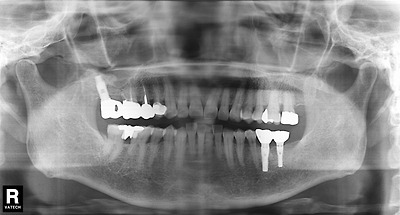

다음 두 사진에서 어떤 차이가 있는지 알아봅시다.

이미지를 클릭하면 원본을 보실 수 있습니다.

힌트; 36번 임플란트 보철물을 살펴보세요.

뭔가 차이점이 보이는군요.

위 사진의 보철물에서는 임플란트의 보철물이 임플란트 굵기보다 더 굵은 것 같습니다.

꼭 작은 머리에 큰 모자를 덮어 씌운 것 같습니다.

그래서 보철물을 재제작한 것이 아래의 사진입니다.